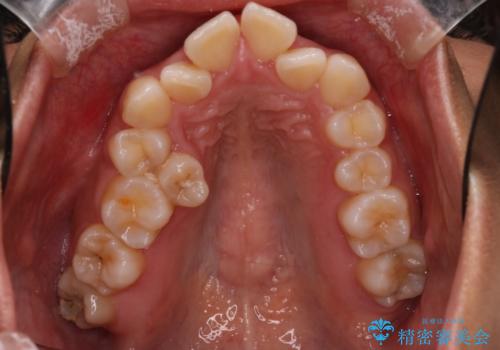

- 前歯の凸凹を主訴に来院されました。

抜歯を行い、ワイヤー矯正にて治療を行いました。

凸凹もなくなり、歯磨きもしやすくなったと喜んでいただきました。

CTにて骨を確認し、側切歯の歯根をこれ以上頬側に出せないことを確認しています。